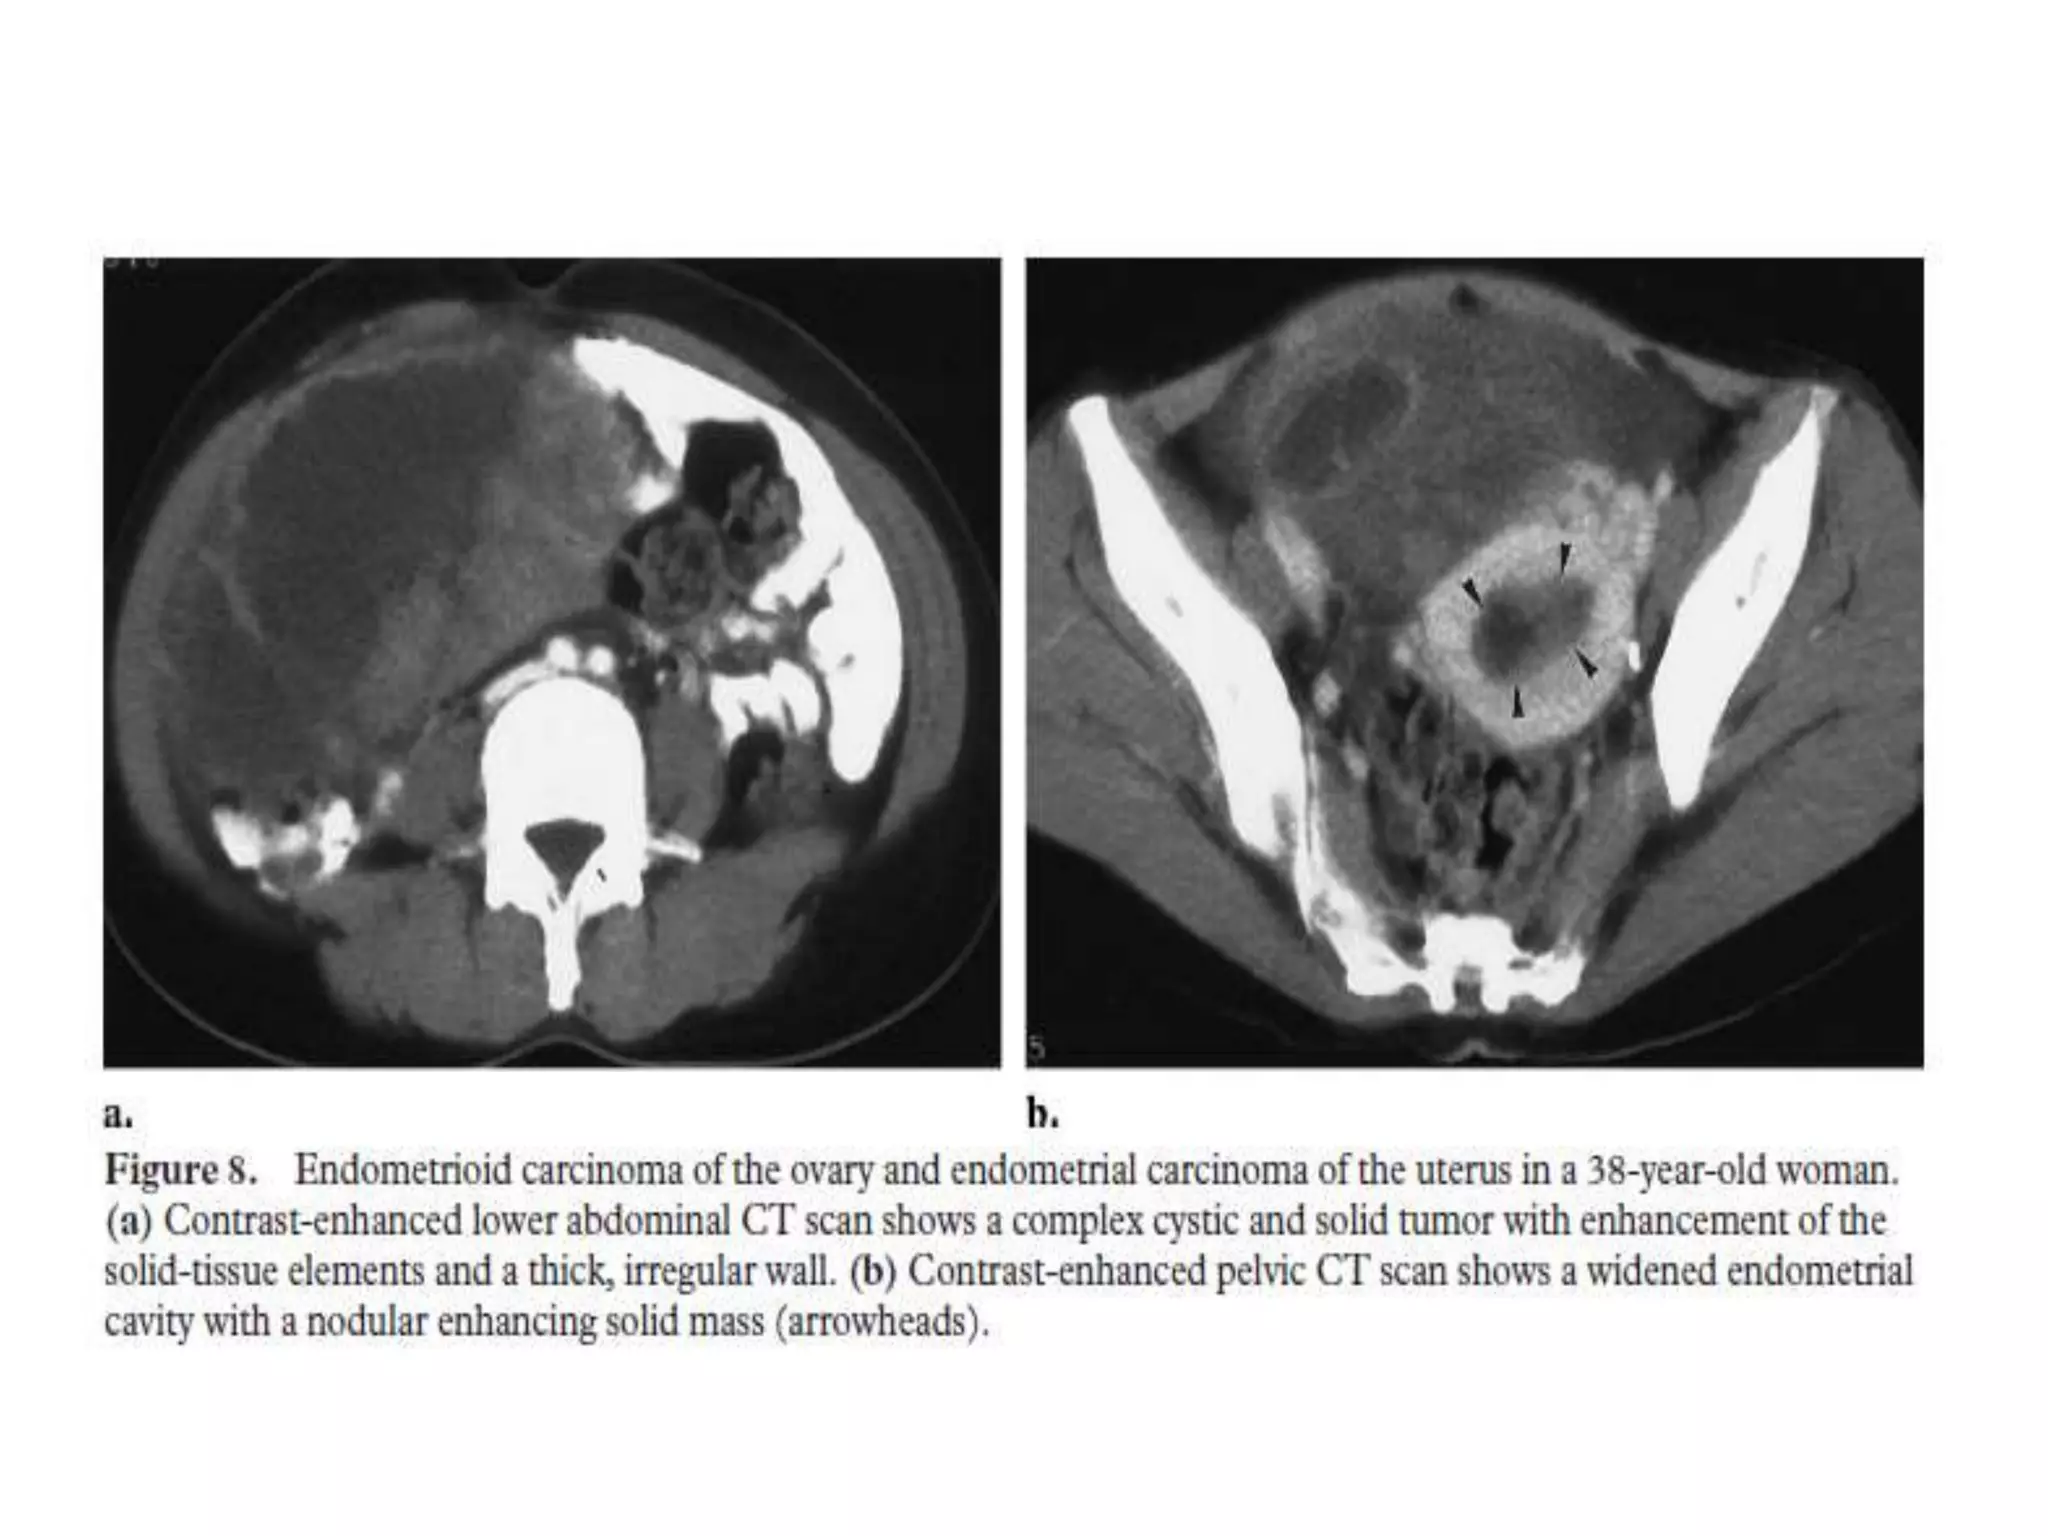

Endometrioid Carcinoma

• Endometrioid carcinomas represent approximately 10%–15% of all ovarian

carcinomas.

• They are almost always malignant.

• About 15%–30% are associated with synchronous endometrial carcinoma

or endometrial hyperplasia.

• Although rare, endometrioid carcinoma is the most common malignant

neoplasm arising from endometriosis, followed by clear cell carcinoma.

• Bilateral involvement is seen in 30%– 50% of cases.

• Imaging findings are nonspecific and include a large, complex cystic mass

with solid components.

• Endometrial thickening can be seen on imaging studies.

Endometrioid Carcinoma • Endometrioidcarcinomas represent approximately 10%–15% of all ovarian carcinomas. • They are almost always malignant. • About 15%–30% are associated with synchronous endometrial carcinoma or endometrial hyperplasia. • Although rare, endometrioid carcinoma is the most common malignant neoplasm arising from endometriosis, followed by clear cell carcinoma. • Bilateral involvement is seen in 30%– 50% of cases. • Imaging findings are nonspecific and include a large, complex cystic mass with solid components. • Endometrial thickening can be seen on imaging studies.